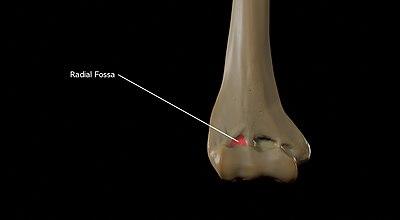

Fossae

Above the front part of the capitulum is a slight depression, the radial fossa, which receives the anterior border of the head of the radius, when the forearm is flexed.

Radial Fossa of the Humerus